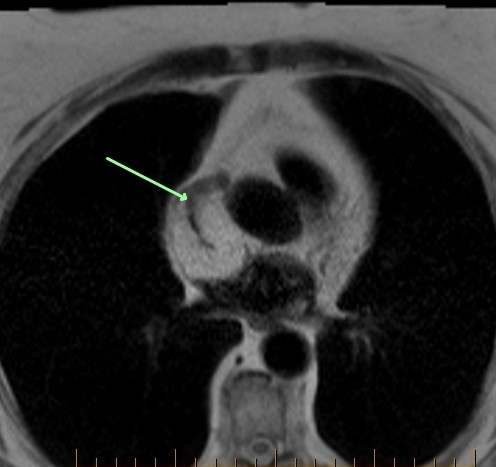

The squeeze play here is a fatty tumor compressing the superior vena cava. The vena cava is normally round. Here, it appears squeezed or slit-like (second image, arrow). This could lead to superior vena cava syndrome. Surveillance recommended every 6 months. The third MR image shows signs of right ventricular dysplasia. The anterior right ventricle is lobulated, irregular and exhibits sparse fat signal.